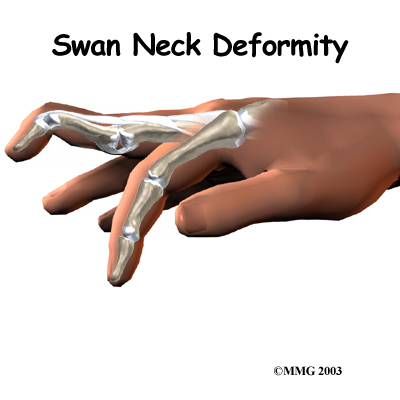

Swan Neck Deformity of the Finger

Normal finger position and movement occur from the balanced actions of many important structures. Ligaments support the finger joints. Muscles hold and move the fingers. Tendons help control the fine motion of each finger joint. Disease or injury can disturb the balance in these structures, altering normal finger alignment and function. The result may be a crooked finger, such as a swan neck deformity of the finger.